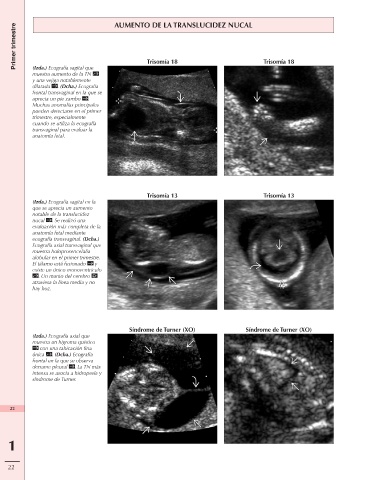

Primer trimestre AUMENTO DE LA TRANSLUCIDEZ NUCAL

(Izda.) Ecografía sagital que

muestra aumento de la TN Trisomía 18 Trisomía 18

y una vejiga notablemente

dilatada . (Dcha.) Ecografía

frontal transvaginal en la que se

aprecia un pie zambo .

Muchas anomalías principales

pueden detectarse en el primer

trimestre, especialmente

cuando se utiliza la ecografía

transvaginal para evaluar la

anatomía fetal.

Trisomía 13 Trisomía 13

(Izda.) Ecografía sagital en la

que se aprecia un aumento

notable de la translucidez

nucal . Se realizó una

evaluación más completa de la

anatomía fetal mediante

ecografía transvaginal. (Dcha.)

Ecografía axial transvaginal que

muestra holoprosencefalia

alobular en el primer trimestre.

El tálamo está fusionado y

existe un único monoventrículo

. Un manto del cerebro

atraviesa la línea media y no

hay hoz.

Síndrome de Turner (XO) Síndrome de Turner (XO)

(Izda.) Ecografía axial que

muestra un higroma quístico

con una tabicación fina

única . (Dcha.) Ecografía

frontal en la que se observa

derrame pleural . La TN más

intensa se asocia a hidropesía y

síndrome de Turner.